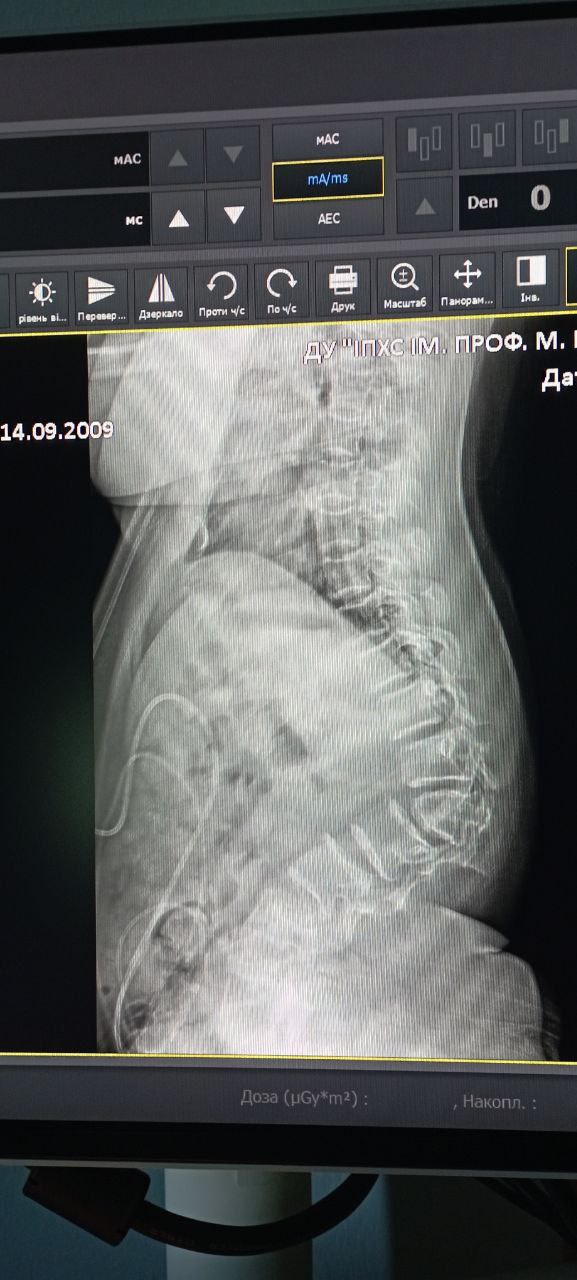

Наш Ромчик успішно переніс довгоочікувану операцію з корекції деформації хребта та фіксації полісегментарною конструкцією яку придбав БФ "Бонум Україна"

Операція була дуже складною, тривала майже 7 годин, але за словами лікарів все пройшло добре.